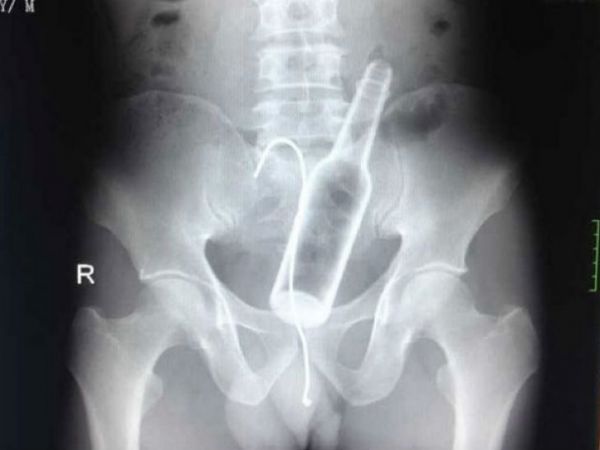

В одну из китайских больниц пришел мужчина с жалобами на боли в животе. Врачи сделали рентгеновский снимок и обнаружили стеклянную бутылку в желудке.